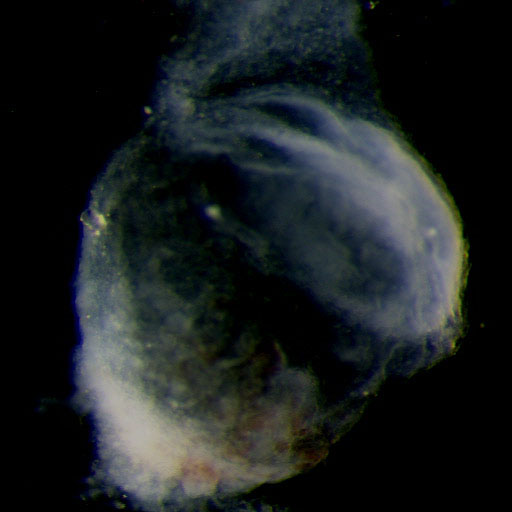

Carnegie Stage 8

Carnegie Stage 8 Definition

Age is approximately 23 postovulatory days

Length is approximately 1 - 1.5mm

External Features Include: the appearance of the primitive pit and the notochordal canal. Somites are not yet visible.